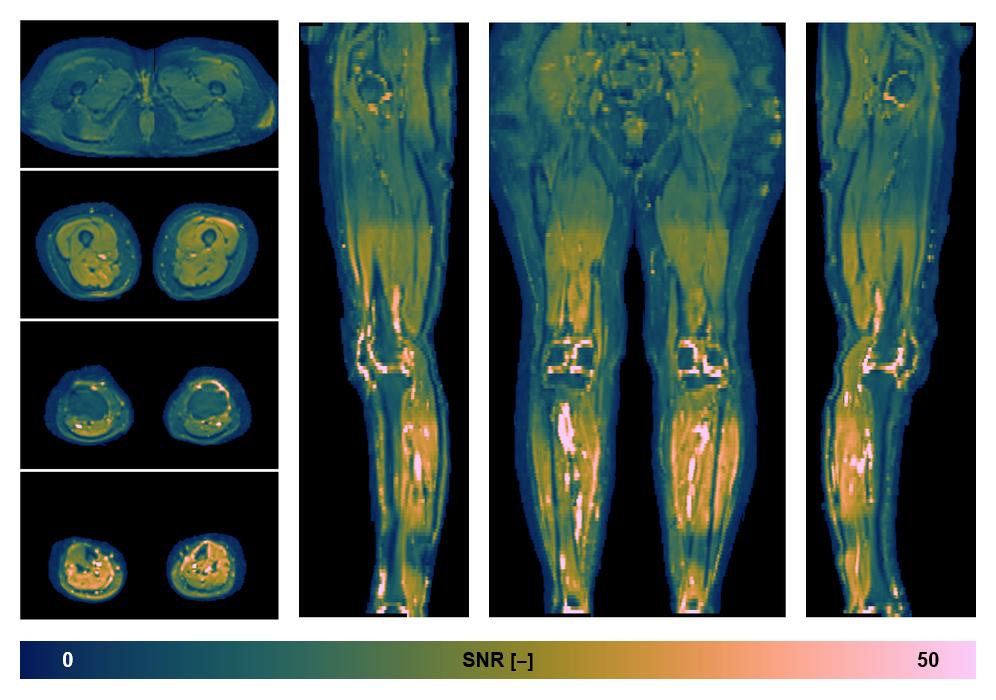

• SNR of the unweighted image

SNR distribution of the unweighted diffusion data.